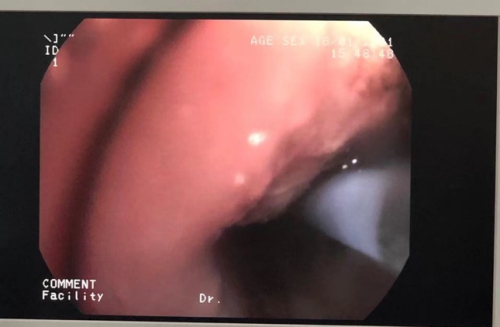

1月13日,一名肖姓肺癌晚期患者,入院后胸闷气逼明显,胸部CT检查提示左肺上叶支气管被肿块阻塞。根据患者疾病情况,科室经过详细讨论决定对该患者进行全麻下经硬质支气管镜介入治疗。为保证首次硬质气管镜置入的顺利,科室缜密设计治疗方案,邀请了院外专家现场指导,并与麻醉科密切协作,充分做好患者术前谈话及评估。首次操作由吴西雅主任医师执行,科主任肖祖克、科副主任涂红缨及科室其他医生均在现场观摩,麻醉科主任张明生实施麻醉。在顺利地将硬质气管镜经口腔过声门入主气管后,吴西雅联合软支气管镜进行支气管内肿瘤消融术,接着行球囊扩张。术中见大量脓性分泌物溢出,吴西雅及时予以清除,术后患者支气管管腔明显通畅,胸闷气逼的症状明显缓解。此次介入治疗约40分钟,术后1小时患者清醒,状态良好。

在专家的现场指导下,吴西雅顺利地将硬镜插入右肺中叶。接下来的操作因为有了硬镜鞘管的气道保护和操作孔道,软镜和冷热消融操作较稳妥。1小时后,李先生右肺下叶支气管顺利打通。术毕患者约50分钟后清醒,气促情况明显缓解,状态良好,未感特殊不适。

冷冻仪冻取、冻溶打通管腔

氩气刀对肿瘤组织进行热消融

操作前后照片对比